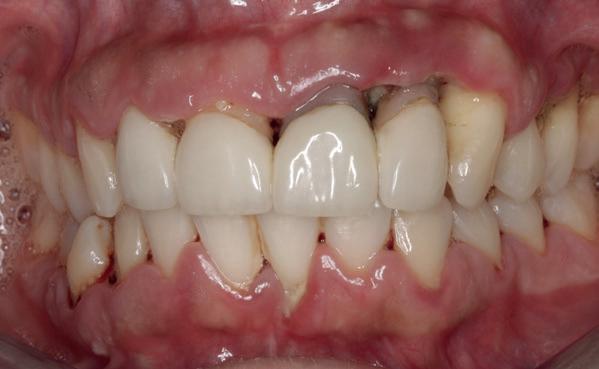

De patiënt, een 70-jarige man, had in het verleden tandheelkundige zorg ontvangen die zich kenmerkte door een ad hoc benadering. Er was geen sprake van een overkoepelend behandelplan of lange termijnvisie. De patiënt had naar eigen zeggen jarenlang niets

1. Studiofoto intake

aan zijn gebit gedaan behalve pappen en nathouden. Tandheelkundige zorg werd enkel verleend wanneer er zich een probleem voordeed (afbeelding 1, 3, 5).

De patiënt werd in de eerste fase gezien door de parodontoloog, implantoloog en restauratief behandelaar. Klinisch werden drie complicerende factoren vastgesteld: inadequate mondhygiëne, een ongunstige occlusale relatie en restauraties met gebrekkige marginale adaptatie met overhang. De patiënt werd opgenomen in het parodontale behandelprotocol.

De diagnose luidde lokaal parodontitis met ernstige furcatie aandoeningen; Stadium IV (vergevorderd); graad C (snel progressief) (afbeelding 7) De elementen die niet te behouden waren, werden geëxtraheerd.

Na afronding van de eerste twee behandelstappen werd parodontale stabiliteit bereikt, zoals waarneembaar op de parodontiumstatus en (röntgen)foto’s (afbeelding 6, 8). De patiënt toonde aantoonbare verbetering in mondhygiëne (afbeelding 4) en bleef gemotiveerd om de behandeling voort te zetten.

3. Lichtfoto intake

4. Lichtfoto na infectie controle